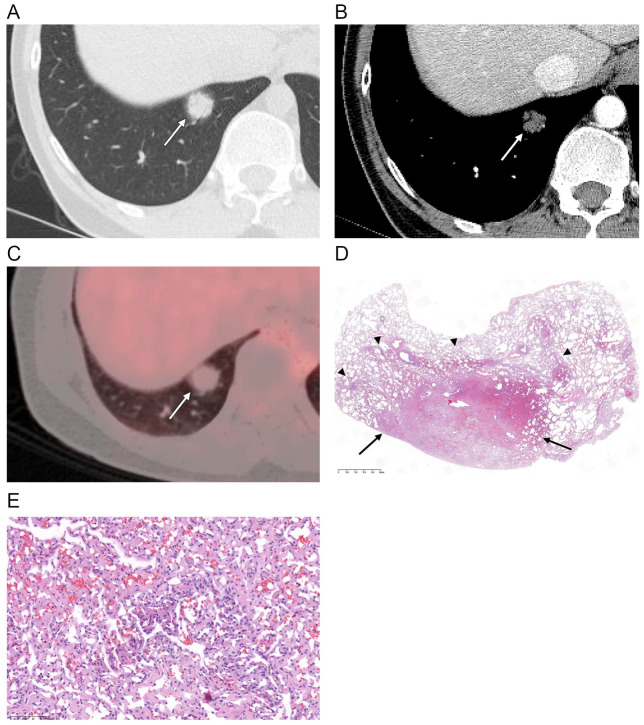

本研究的目的是评价孤立性肺毛细血管瘤(SPCH)的CT和PET-CT表现与临床病理的相关性。本回顾性研究包括来自四所高等院校的17例组织学证实的SPCH患者。本文对SPCH的临床、病理及影像学表现进行综述。评估的CT特征包括病灶位置、大小、密度、轮廓、边缘、增强、支气管充气征的存在、血管周围透光和胸膜缩回,以及PET-CT上的18f -氟脱氧葡萄糖摄取。在随访期间,还评估了大小的变化。影像学表现与临床病理表现相关。患者平均年龄47岁(范围30-60岁)。所有SPCHs都是在筛查CT检查(n = 13,76%)或癌症检查期间偶然发现的(n = 4,24%)。大多数SPCHs表现为半实性结节(n = 15.88%),其余分别表现为纯磨玻璃结节或纯实性结节。大多数具有平滑轮廓(n = 16.94%),而一个具有分叶状轮廓。9家SPCHs(53%)的利润率不明确。10例(59%)SPCHs存在空气支气管征,2例(12%)血管周围透光。所有SPCHs在增强CT上表现为低衰减,在PET-CT上表现为低代谢。在随访期间(平均14.8±17.7个月),10例(59%)SPCHs病变大小和密度无变化,3例(18%)SPCHs病变大小和密度减小或波动。SPCH常在中青年偶然发现,通常表现为不明确的部分实性结节,CT上可伴有支气管充气征、血管周围透光、大小或密度波动,PET-CT上可伴有代谢低下。

The aim of this study was to evaluate the CT and PET-CT features of solitary pulmonary capillary hemangioma (SPCH) with clinicopathologic correlations. This retrospective study included 17 patients with histologically proven SPCH from four tertiary institutions. The clinical, pathological and imaging findings of SPCH were reviewed. The CT features assessed included lesion location, size, density, contour, margin, enhancement, presence of air bronchogram, perivascular lucency and pleural retraction, and 18F-fluorodeoxyglucose uptake on PET-CT. Changes in the size during the follow-up period were also evaluated. Imaging features were correlated with the clinicopathologic findings. The mean age of the patients was 47 years (range 30-60 years). All SPCHs were incidentally detected during screening CT examinations (n = 13, 76%) or during cancer work-up (n = 4, 24%). Most SPCHs appeared as part-solid nodules (n = 15, 88%), the remaining appeared as a pure ground-glass nodule or a pure solid nodule, respectively. Most had smooth contours (n = 16, 94%), while one had a lobulated contour. Nine SPCHs (53%) showed ill-defined margins. Air bronchogram was present in ten (59%) SPCHs, and perivascular lucency in two (12%). All SPCHs exhibited hypoattenuation on contrast-enhanced CT and hypometabolism on PET-CT. During the follow-up period (mean 14.8 ± 17.7 months), the lesions showed no change in size or density in ten SPCHs (59%), decreased or fluctuation in size and density in three (18%). SPCH is often incidentally detected in young and middle-aged adults, commonly as an ill-defined part-solid nodule that may accompany air bronchogram, perivascular lucency, and fluctuation in size or density on CT and hypometabolism on PET-CT.